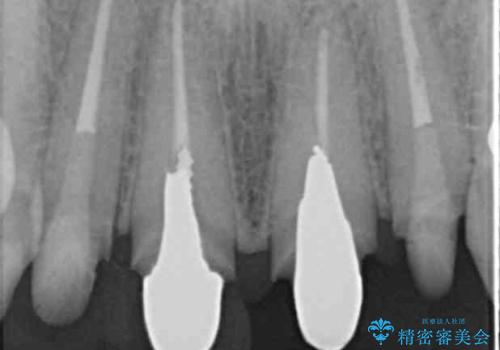

- 「黒ずみの前立つ前歯をやりかえ、きれいにしたい。」と希望され来院されました。

金属色の目立つ前装冠を除去し、発生していた小さな虫歯を丁寧に全て除去しジルコニアセラミッククラウンで審美的な前歯となるような治療を計画します。